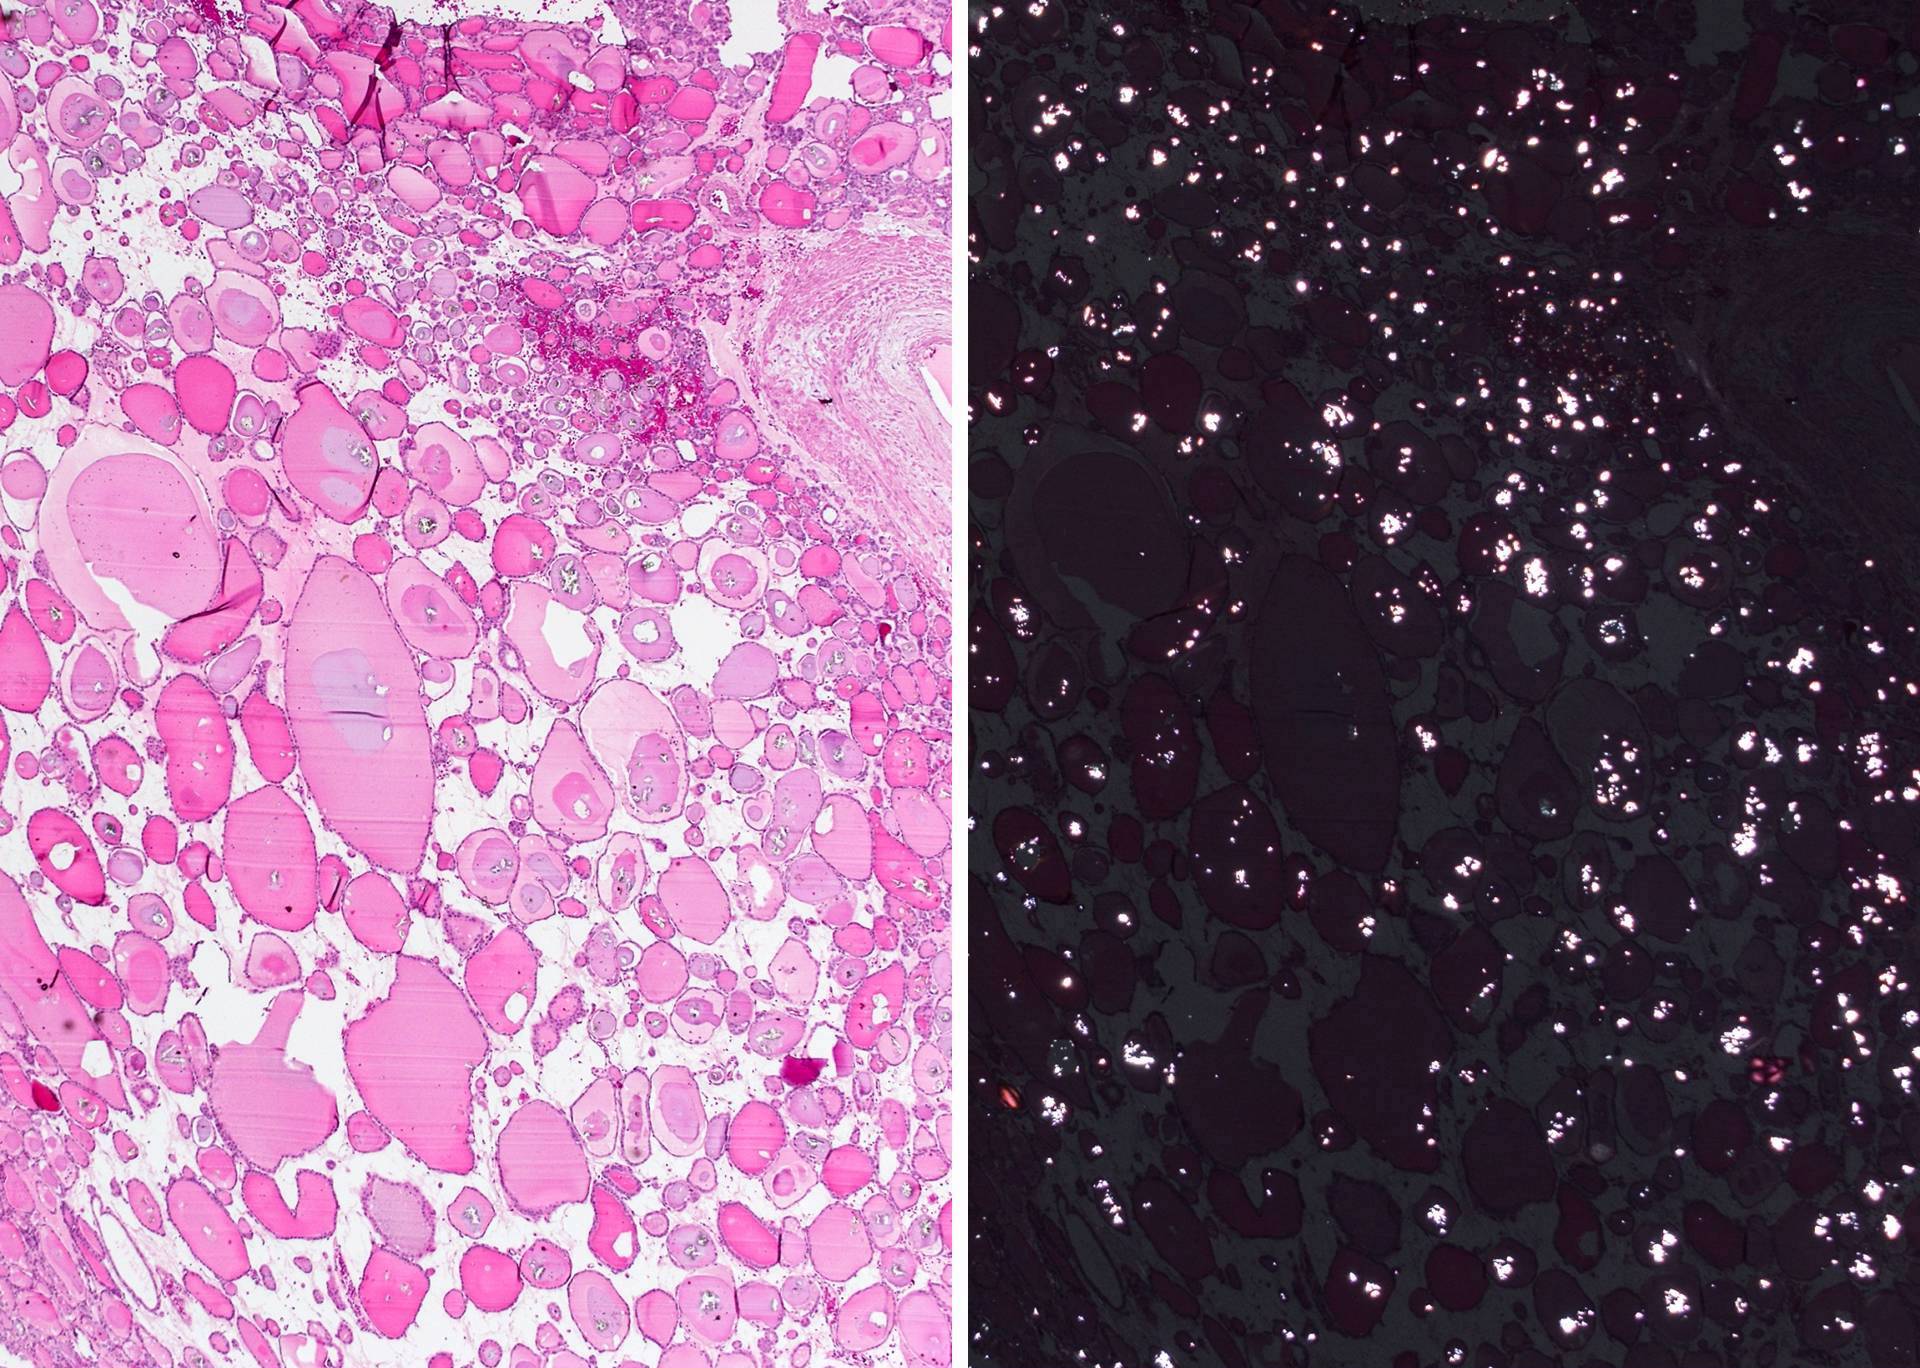

Microscopic (histologic) description

- Encapsulated; thin or moderately thick capsule

- Macrofollicular (colloid): large follicles, flattened epithelium, abundant colloid

- Secondary changes: fibrosis, hyalinization, hemorrhage, hemosiderin deposition, edema, cystic degeneration, calcification, osseous or cartilaginous metaplasia

Microscopic (histologic) images

Contributed by Shipra Agarwal, M.D., Andrey Bychkov, M.D., Ph.D., Mark R. Wick, M.D., Asmaa Gaber Abdou, M.D. and AFIP

Patterns:

Atypical adenomas:

Not invasion: